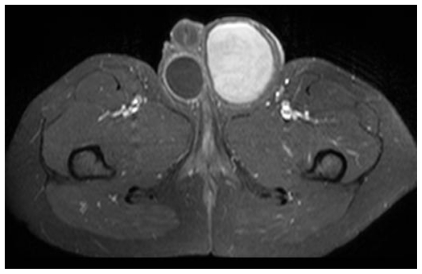

Figure 2.

24 Year old male with large hemorrhagic abdominolscrotal hydrocele: TSE T1-weighted axial plane. The left scrotal wall appears thickened, particularly on the left side and on the back. The content is heterogeneously hyperintense, possibly due to blood.